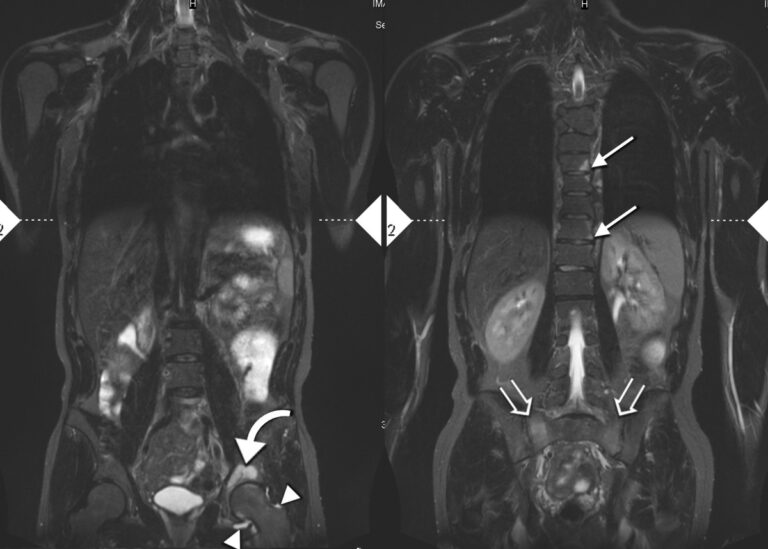

Průměrná doba diagnózy Bechtěrevovy nemoci je devět let

Bechtěrevova nemoc je nenápadná, nevypočitatelná a zákeřná. Tuhnou při ní klouby a postupem času vede k úplnému ztuhnutí páteře. Lidé ji ale často zaměňují za běžnou bolest zad a průměrně trvá až dlouhých devět let, než ji lékaři správně diagnostikují. Včasná diagnóza a nasazení vhodné léčby by přitom mohly zpomalit rozvoj nemoci a pacienti by […]

Na správnou diagnózu čekají lidé se sklerodermií roky

Poporodní deprese, lupus, hypochondrie. I tyto diagnózy si vyslechli pacienti, než u nich lékaři odhalili systémovou sklerodermii. Vyplývá to z dotazníku, který mezi nemocné rozeslala pacientská skupina Skleroderma Revma Liga Česká republika. Téměř 30 % z dotázaných si svoji skutečnou diagnózu vyslechlo až za 10 let od prvních příznaků nemoci. Roky tak prožili v nejistotě, […]